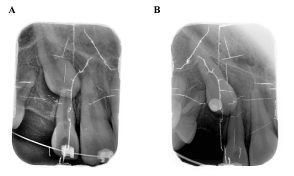

0.022 slot Roth brackets had been bonded on all upper and lower teeth except #12 which acted as a free body initially till the canine had been moved away from its root (Figure 3). After 6 months of alignment, space started to be created for the canine using opening coil spring (0.010 x 0.035 inch) (Figure 4). The first stage of surgery was planned to be VISTA technique in order to move the canine horizontally and to situate the canine crown directly under its socket using the microimplant (MI) (Figures 5 and 6). During surgery, all the bone distal to the canine crown till its CEJ which is in the way of its movement had been removed. A microimplant from (Ormco) VectorTas of 2 x 8 mm had been placed in the infrazygomatic crest parallel to the upper right first molar (Figure 7). A lingual button bonded on the labial surface of the canine and connected to the microimplant via a power chain which was passing under the alveolar mucosa over the canine. The horizontal movement of the crown had been activated every month by cutting a hole from the power chain. A panoramic periapical radiograph A-B taken directly after MI placement and 3 months over that to control the movement of the canine (Figures 8 and 9). After 3 months of horizontal movement of the canine, the patient referred again for the 2nd stage of surgery where a full reflected flap performed in order to remove the old power chain and place new one which is directly connected to the main archwire (Figure 10). All the bone above the canine crown till the 2 mm from the alveolar crest had been removed in order to facilitate the tooth movement vertically. The main arch wire which is 0.017x0.025 Stst had been offset in the area between #12, 14 (Figure 11). This offset placed to help for keeping the canine root in the alveolar bone and avoid the labial tipping of the crown. A crimpable attachment with a hook fixed on the wire directly over the canine crown and a power chain connected directly from the lingual button to the hook (Figure 12). The vertical movement of the crown had been activated every month by cutting a hole from the power chain. After the canine came out of the soft tissue a bracket bonded and thin wire placed in its slot with a sequence of 0.12 Niti, 0.14 Niti, 0.16 Niti, 0.16 x 0.22 Niti, 0.16 x 0.22 Stst, 0.17 x 0.25 Niti and 0.17 x 0.25 Stst. Canine root torque had been checked after its reaching to the occlusal plane and found that no need for any adjustment since it is similar with the opposing canine root eminence (Figure 13). After 24 months of active treatment, all appliances were debonded (Figure 14). Orthopantogram, lateral cephalography and periapical radiograph had been taken to record as a baseline for future follow up and assessment. Clear overlays delivered for both arches as retainers with proper instructions (Figure 15).

Figure 9. A- Intra oral radiograph immediately before horizontal movement of #13; B-3 months post traction #13